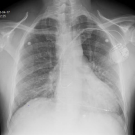

A 63-year-old white woman presented for continued workup for shortness of breath and an ongoing cough.